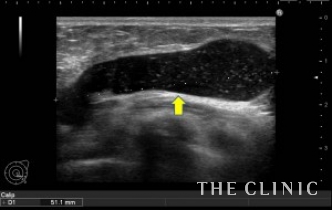

3年前に他院にてヒアルロン酸豊胸を受けられて、左だけしこりを感じるようになりご主人からは癌ではないかと指摘されたそうです。自分ではヒアルロン酸だと思ってはいたようですが、念のためエコーでの診察と治療までをご希望でご来院されました。

エコーで診てみると、右はほとんど吸収されていますが、左のしこりは最大で5cm以上で、小さなしこりも散在しているのが分かります。